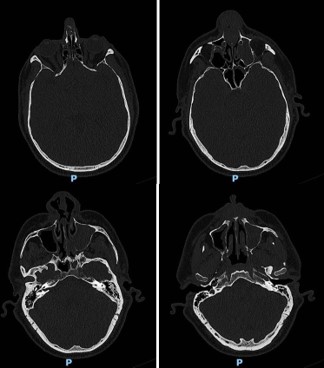

The ostiomeatal complexes were occluded bilaterally, and there was bowing of the nasal septum to the right (Figure 1). He was scheduled for an endoscopic evaluation under anesthesia with nasal biopsy and frozen section analysis. Intraoperatively patient was noted to have fungating masses within bilateral nasal cavities. Multiple biopsies were obtained showing invasive squamous cell carcinoma. The case was terminated and a CT neck with contrast was obtained for surgical planning.

The new CT showed an ulcerated mass within the nasal cavity and a 1.4 cm septal perforation. Fluid and soft tissue were completely opacifying the left maxillary sinus. There was destruction of the nasal bone with the involvement of nasal skin, septal destruction with extension to the hard palate, and an extensive mass inside of the left maxillary sinus without any apparent orbital floor invasion (Figure 2). No cervical or distant metastases were appreciated at the time. The clinical Tumor, Nodal, and Metastasis (TNM) staging for the tumor was noted to be cT4N0M0. We recommended a left maxillectomy, left modified neck dissection with subtotal rhinectomy, and left chimeric scapular free flap for reconstruction.

Figure 1: Preoperative CT of facial bones, showing maxillary bony invasion, soft tissue mass, and maxillary opacification.

Figure 2: CT neck with contrast, showing ulcerated mass within nasal cavity, septal perforation, invasion of the maxilla and nasal skin involvement.